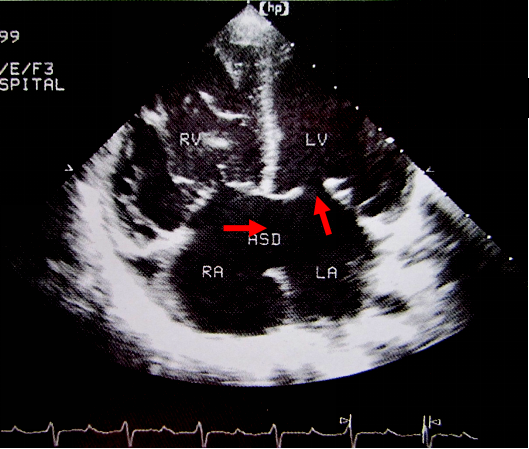

房间隔缺损:超声心动图表现

房间隔缺损(原发孔型)合并二尖瓣裂缺